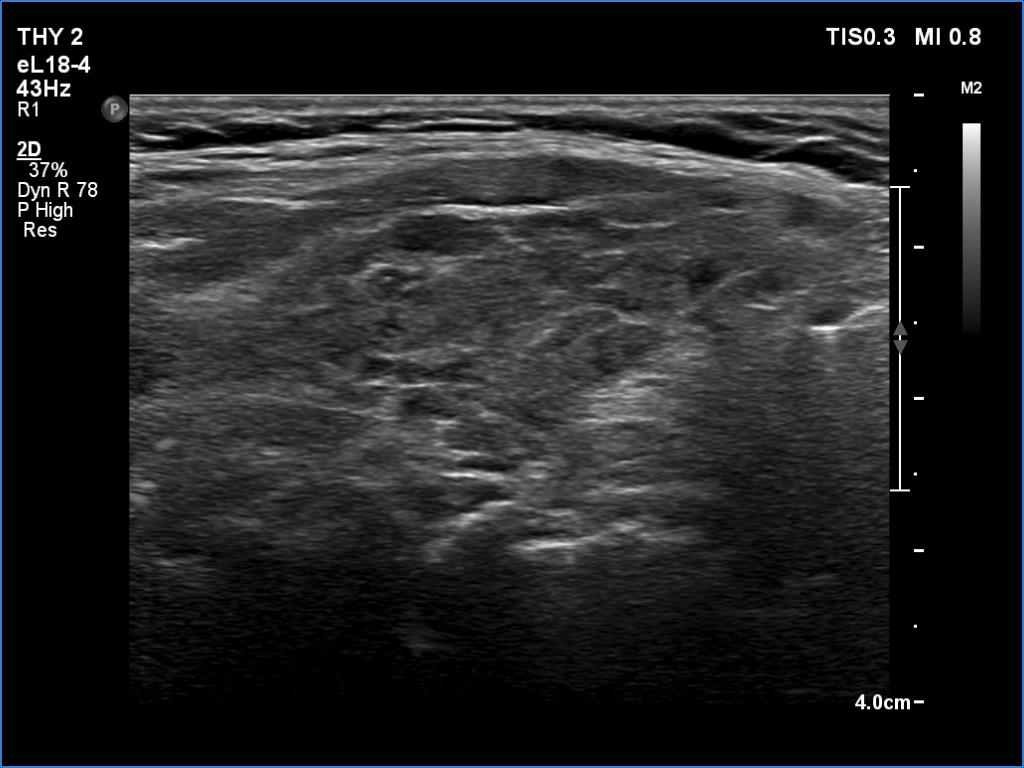

Lymphocytic thyroiditis - case 751

Right lobe

Focal form of lymphocytic thyroiditis is presented. The thyroid has numerous discrete, hypoechoic lesions which correspond to more active foci of thyroiditis. The interpretation of this pattern should not cause concern - these areas are not pathological nodules. The discrete lesions have non-regular, partly clearly lobulated or spiculated margins.